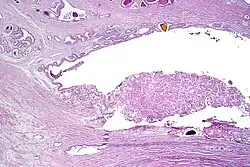

Intraductal carcinoma

Intraductal carcinoma of the prostate gland (IDCP), which is now categorised as a distinct entity by WHO 2016, includes two biologically distinct diseases. IDCP associated with invasive carcinoma (IDCP-inv) generally represents a growth pattern of invasive prostatic adenocarcinoma while the rarely encountered pure IDCP is a precursor of prostate cancer.[20] The diagnostic criterion of nuclear size at least 6 times normal is ambiguous as size could refer to either nuclear area or diameter. If area, then this criterion could be re-defined as nuclear diameter at least three times normal as it is difficult to visually compare area of nuclei.[20] It is also unclear whether IDCP could also include tumors with ductal morphology.[20] There is no consensus whether pure IDCP in needle biopsies should be managed with re-biopsy or radical therapy. A pragmatic approach would be to recommend radical therapy only for extensive pure IDCP that is morphologically unequivocal for high-grade prostate cancer.[20] Active surveillance is not appropriate when low-grade invasive cancer is associated with IDCP, as such patients usually have unsampled high-grade prostatic adenocarcinoma.[20] It is generally recommended that IDCP component of IDCP-inv should be included in tumor extent but not grade.[20] However, there are good arguments in favor of grading IDCP associated with invasive cancer.[20] WHO 2016 recommends that IDCP should not be graded, but it is unclear whether this applies to both pure IDCP and IDCP-inv.[20]

Intraductal carcinoma of the prostate with an infiltrative growth pattern may be morphologically difficult to distinguish from invasive cancer. One focus shows comedonecrosis (arrow), morphologically suggesting Gleason pattern 5 invasive carcinoma (a haematoxylin and eosin, b CK5/6)[20]

Intraductal carcinoma of the prostate with very patchy basal cells identified by immunohistochemistry. At least some of the glands lacking basal cell immunoreactivity represent intraductal rather than invasive carcinoma (a haematoxylin and eosin, b CK 5/6)[20]